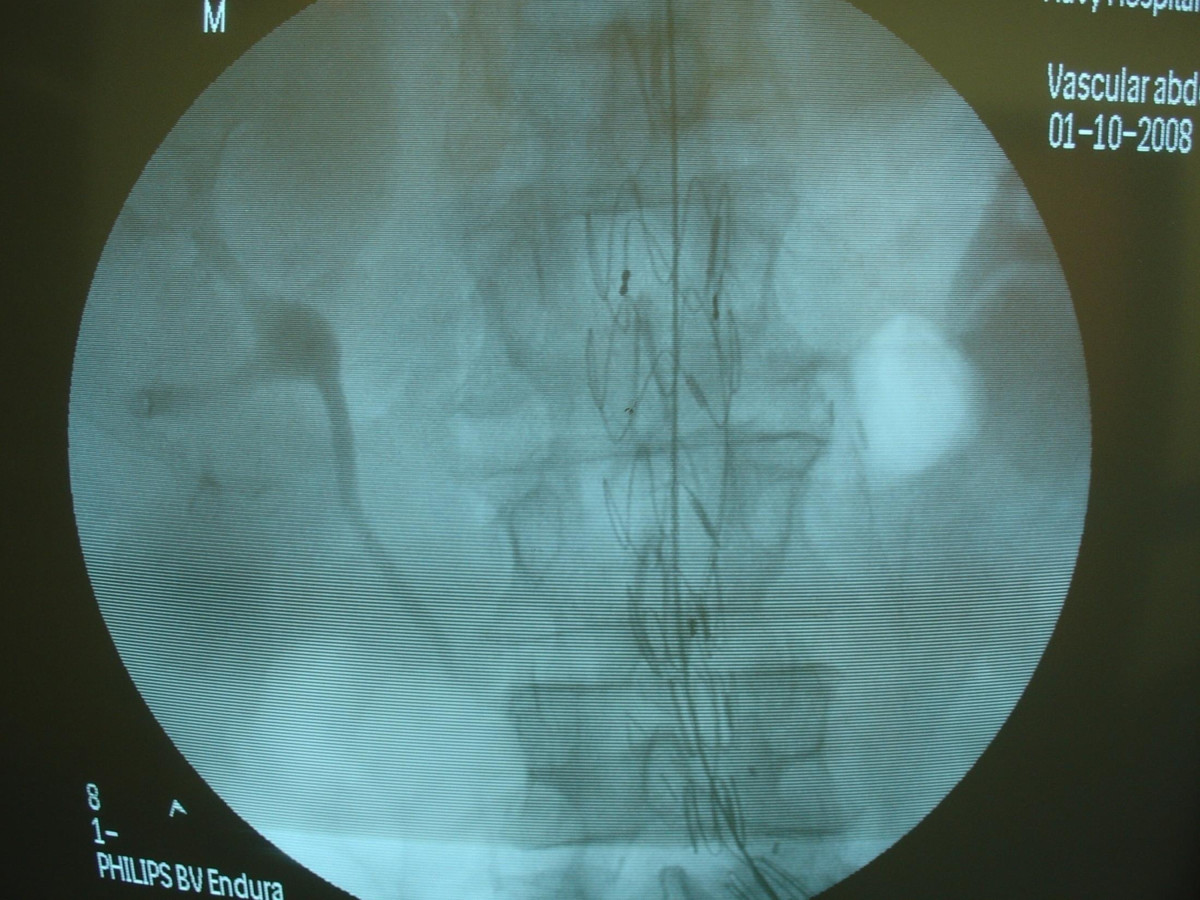

Endovascular repair of anastomotic abdominal aortic aneurysm, after aortobifemoral bypass

Vascular Clinic, Naval and Veterans Hospital of Athens

AVEM2009-Thessaloniki